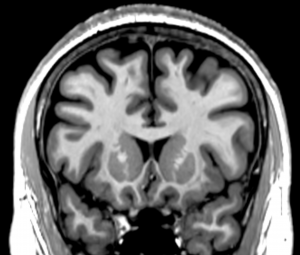

T1

The T1 acquisition comprises a pair of 0.9 mm iso MPRAGE scans. They are accelerated by a factor of 4 as a way to deal with motion. A T1 with no acceleration is about 11 minutes long. The chance of a subject being still for 11 minutes is near zero. The PAT4 scan acquisition time is 3:26; the chance of that being without motion is decent. And, if there is motion, a 3.5 minute scan can be repeated; an 11 minute scan cannot. The acceleration, though, does impact the SNR. SNR drops by roughly the square root of the acceleration factor. That is why there are two T1s. Averaging the two PAT4 T1s returns you to roughly the SNR of a single PAT2 T1, and also reduces the impact of minor motion in either T1. Both T1s are required to be relatively free of motion artifacts. Repeat as necessary.

The T1s are collected with no angles. The position parameters from the first T1 are copied to the second.